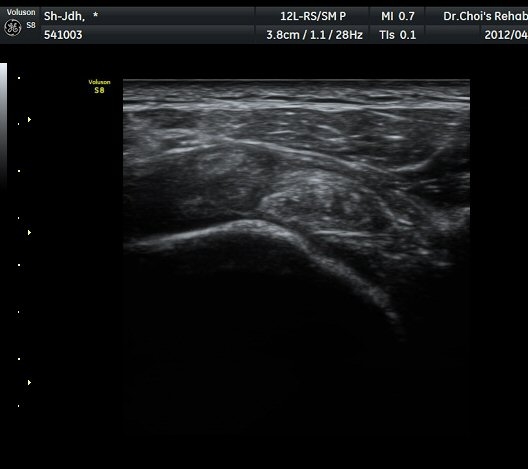

À̵ιڱٰú ÀÌ¿ôÇÑ °ß°©ÇÏ±Ù°Ç »óºÎ¿¡¼­ ±¹¼ÒÀûÀÎ ¿¬°á¼º ¼Ò½ÇÀÌ °üÂûµÊ(»çÁø 3).

¾î±ú µÚ °üÀý¼ø °Ë»ç¿¡¼­ °üÀý¼ø Ç¥Ãþ¿¡ Àú¿¡ÄÚ ¼ö¾×Àú·ù°¡ °üÂûµÊ(»çÁø 4).